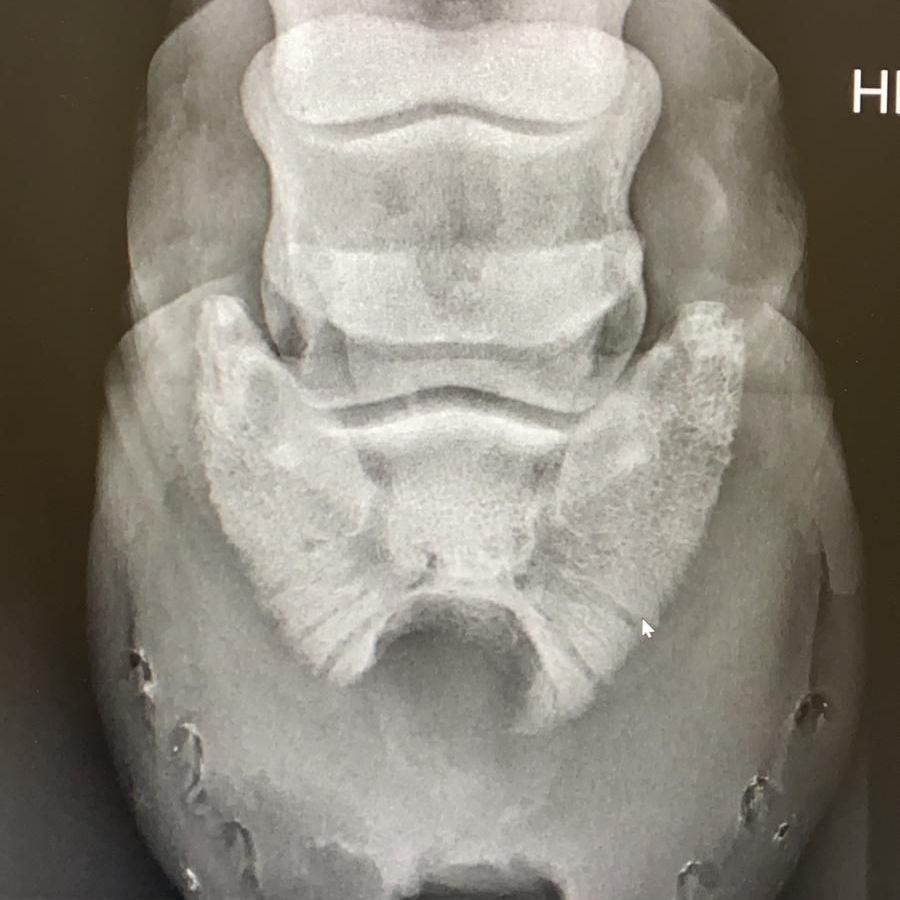

Pferd mit akuter Hufrehe

Hufrehe ist nicht, wie der Name vermuten lässt, eine Hufkrankheit. Es ist eine Stoffwechselerkrankung. Deswegen muss immer erst ein Tierarzt dazu geholt werden. Hufrehe ist IMMER ein Notfall!

Als Hufschmied behandle ich die Nebeneffekte der Krankheit, welche sich an Huf und Beinen vom Pferd manifestieren. Es gibt verschiedene Arten von Hufrehe, welche entweder metabolischen oder mechanischen Ursprung haben. Auch muss ein Unterschied zwischen dem akuten Stadium oder einem chronischen Stadium gemacht werden.